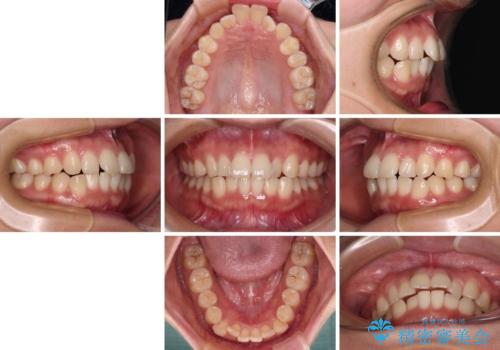

- 上下前歯のデコボコを気にして来院された患者様です。

ワイヤー矯正でもインビザラインでも、どの装置でも対応可能でしたが、安価で楽して素早く治療を終えたいとのことで、メタルブラケット装置による矯正治療を行うこととしました。